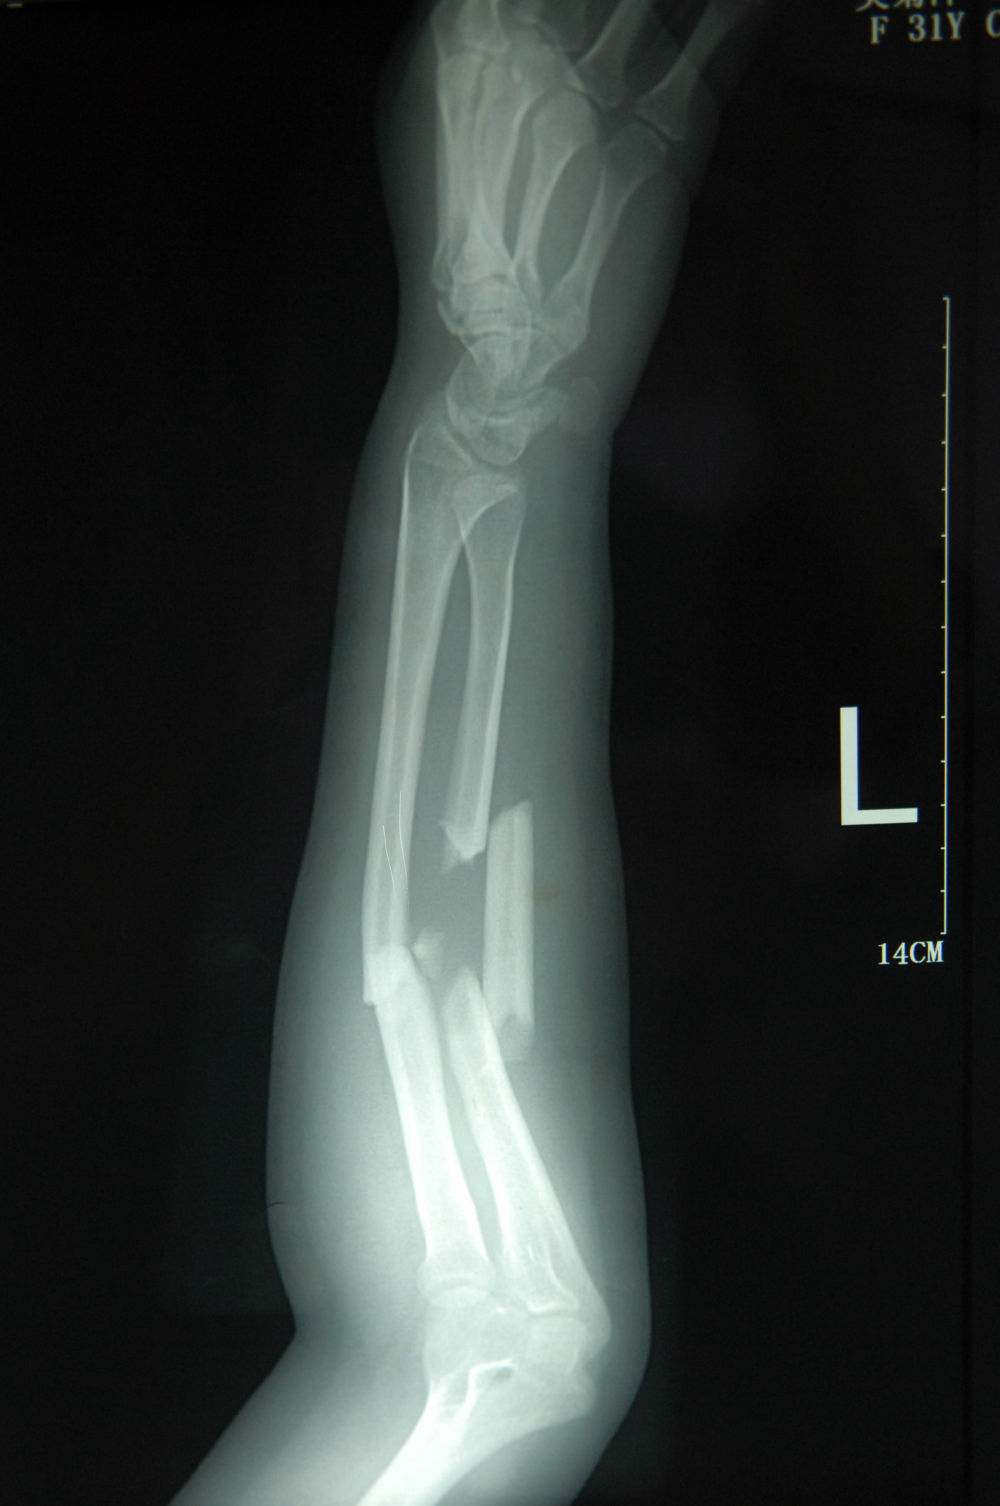

↑这是2011年7月3日拍摄的吴菊萍受伤左臂的X光片,医生诊断为手臂左尺桡骨多段粉碎性骨折。